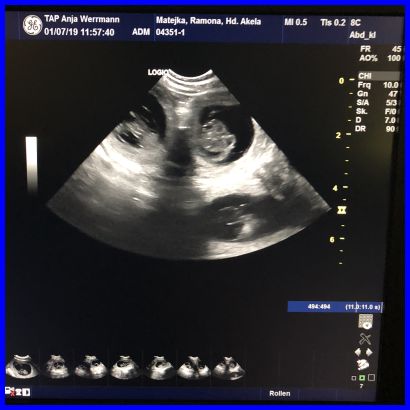

Hier auf diesem Bild kann man sogar drei Föten sehen.